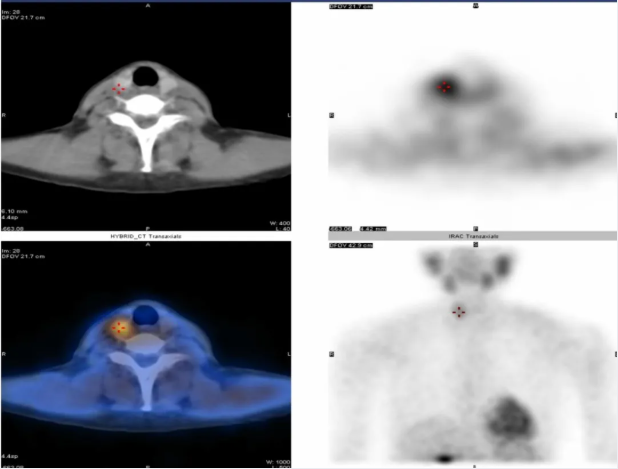

甲状旁腺显像

原发性和继发性甲状旁腺功能亢进的诊断与术前定位;异位甲状旁腺的诊断。

▲甲状旁腺显像